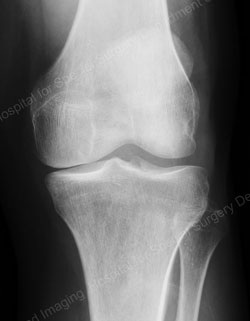

Figure: Example of a fixed bearing unicondylar knee replacement

(the images on top represent a preoperative joint; the images on the bottom represent a postoperative joint)